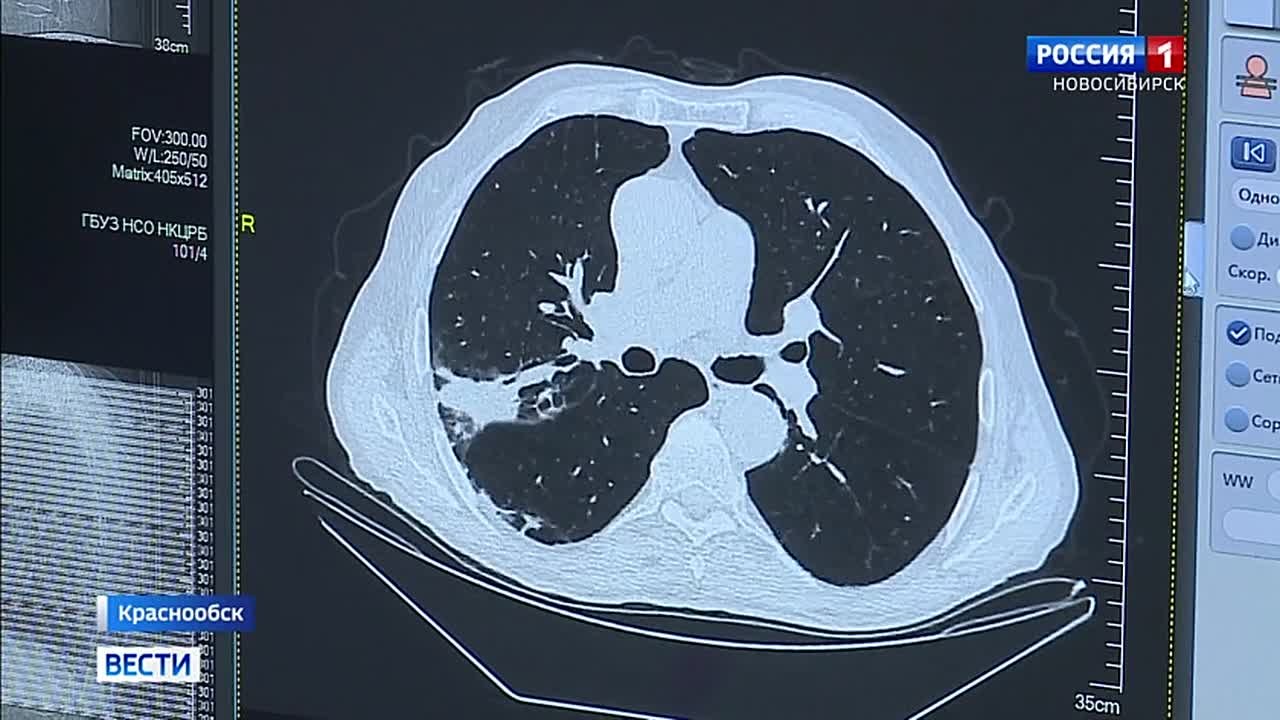

Данный центр оснащён всем современным оборудованием, включая компьютерный томограф, который за пять минут создаёт 3D-модель органа и выявляет опухоли размером в миллиметры.